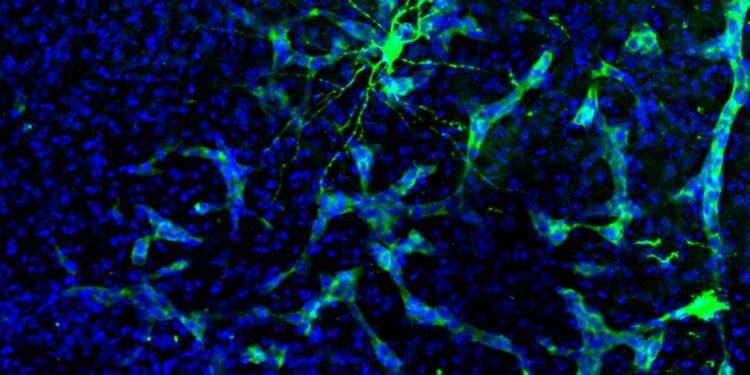

Investigadores del CSIC y del Centro Nacional de Investigaciones Oncológicas (CNIO) han descubierto que los tumores cerebrales, en particular las metástasis, pueden interferir en la comunicación entre las neuronas al alterar la actividad cerebral y su composición química.

Además, los investigadores están explorando cambios bioquímicos que podrían explicar estas alteraciones en la actividad cerebral. Han identificado una molécula llamada EGR1 que podría tener un papel importante en este proceso, lo que podría abrir la puerta al desarrollo de fármacos para prevenir o mitigar los efectos neurocognitivos de las metástasis cerebrales.